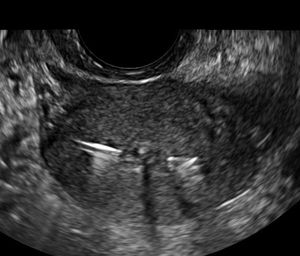

Ultrasound technology can be an indispensable tool for the management of suspected early pregnancy loss.